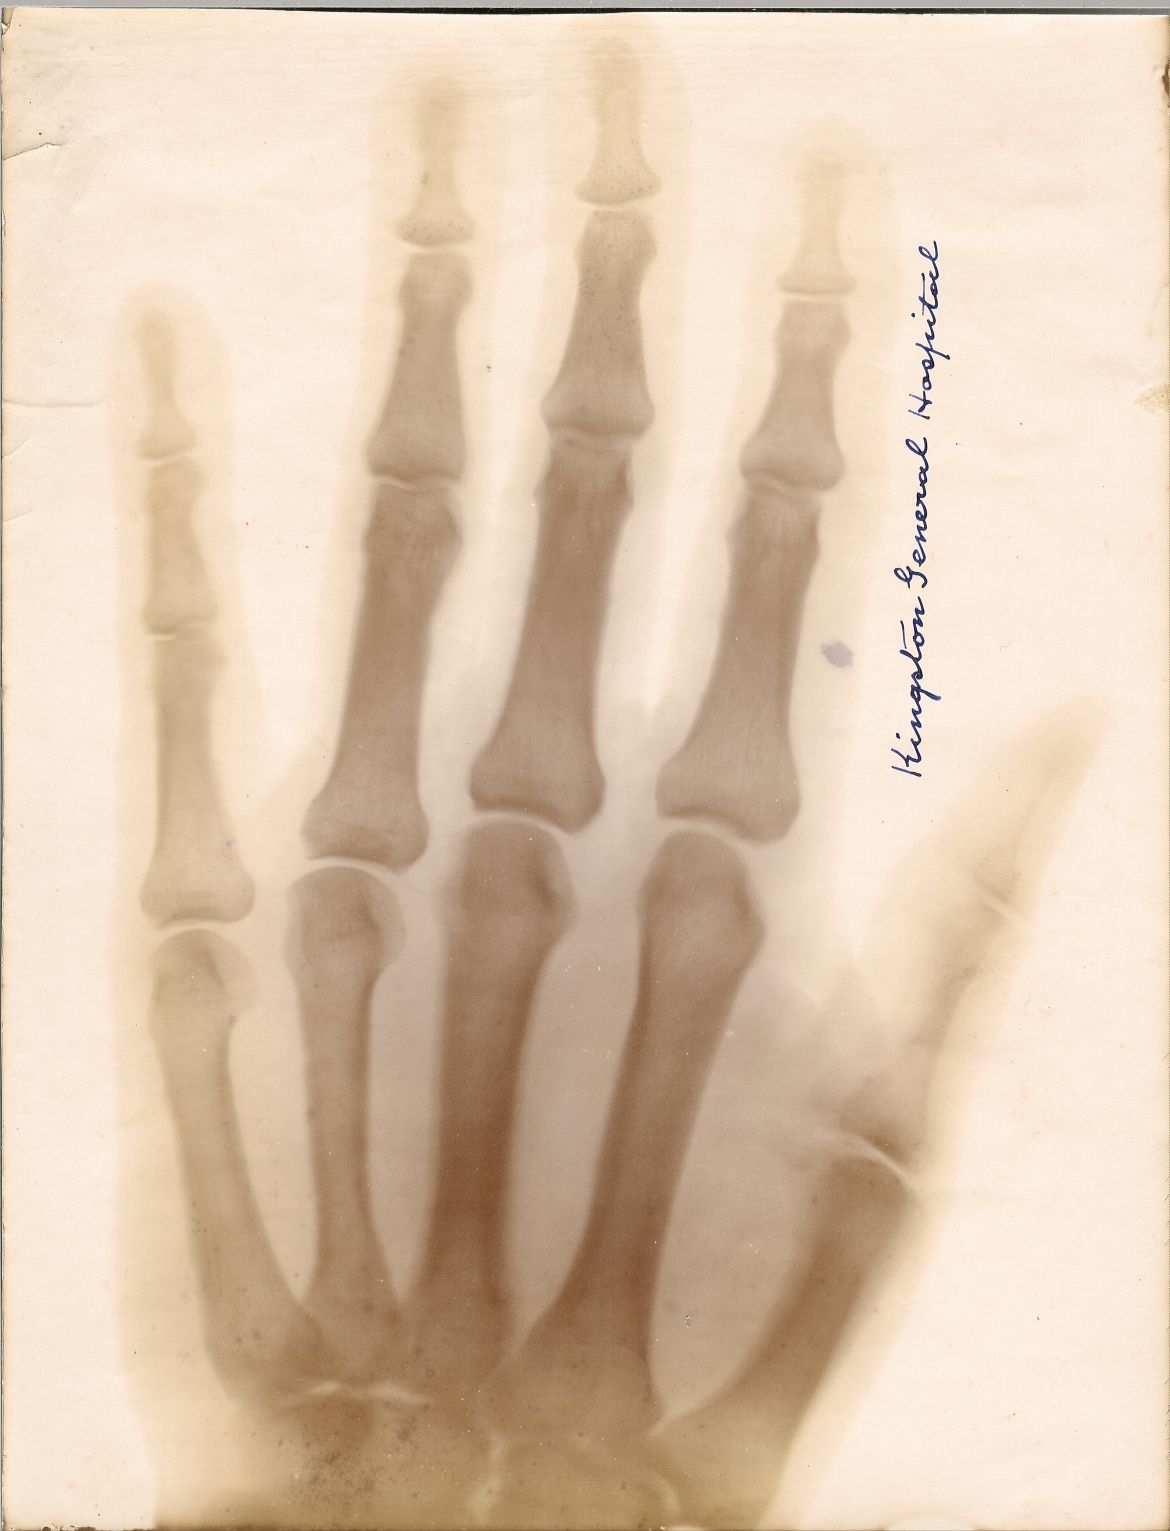

An early X-ray print of a hand